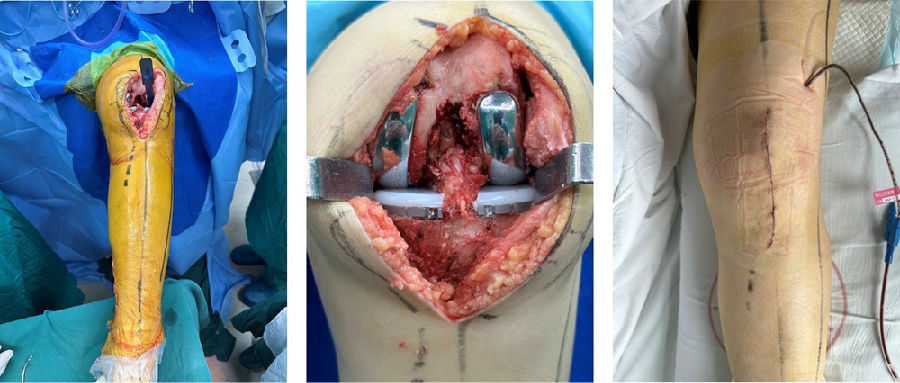

手术切口与暴露。A.膝前正中切口B.髌旁内侧入路C.内侧、外侧股骨髁磨损,ACL功能正常

内侧单髁置换。A.截骨完成B.安装内侧假体,等待骨水泥凝固C.假体安装完成

外侧单髁置换。A.按照外侧假体,等待骨水泥凝固B.内外侧单髁假体安装完毕C.切口及引流